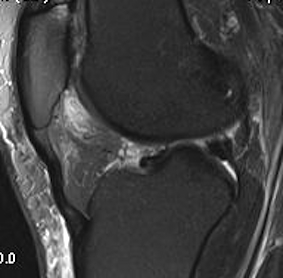

MRI

See increased signal in fat pad